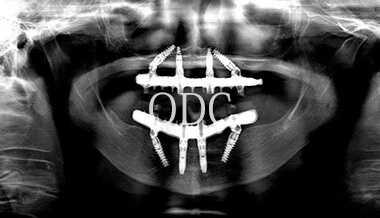

パノラマX線写真

術 前

術 後

術前・術後のパノラマX線写真です。上顎(オールオン4)は4本のインプラントにチタンフレームの上部構造が固定されているのがおわかりになると思います。下顎のインプラント埋入部位、上顎のインプラントの本数、再度写真をご覧いただくと、とてもインプラントが埋入されているとわからない程の外観、下顎の残存歯(元々の自分の歯)とも区別がつかない審美性が実現されています。